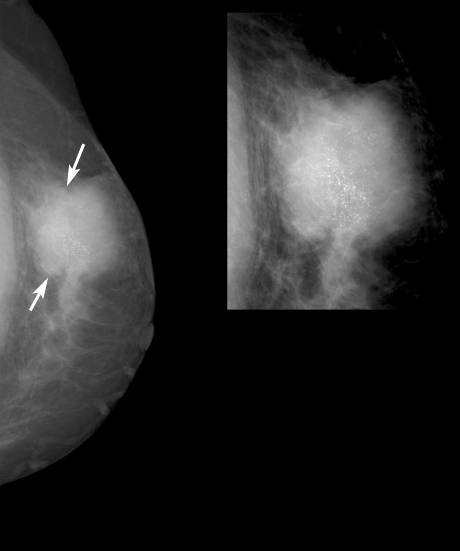

乳腺的良性钙化约占乳腺钙化的80%,恶性钙化常见于乳腺癌或其它肿瘤,约占乳腺钙化的20%。约30%-50%的乳腺癌患者在钼靶片上可显示微小的钙化。影像学主要从两个方面对乳腺钙化进行分析,即:钙化的形态和钙化的分布。良性钙化的“白点”往往表现为粗大的颗粒状(个头比较大,大“白点”)、边缘清楚、形状规则(圆形、卵圆形等),且呈散在分布。恶性钙化的“白点”往往表现为细小砂砾样(个头比较小,小“白点”)、边界模糊、形状不规则,呈一堆堆或一簇簇、一条条状的分布。

乳腺恶性肿块(乳腺癌)伴恶性钙化X线表现:肿块(↑)部分边缘不清,密度较高,肿块内可见细小砂粒状钙化(左上角局部放大图显示钙化更清晰),局部皮下脂肪层混浊,皮肤增厚。